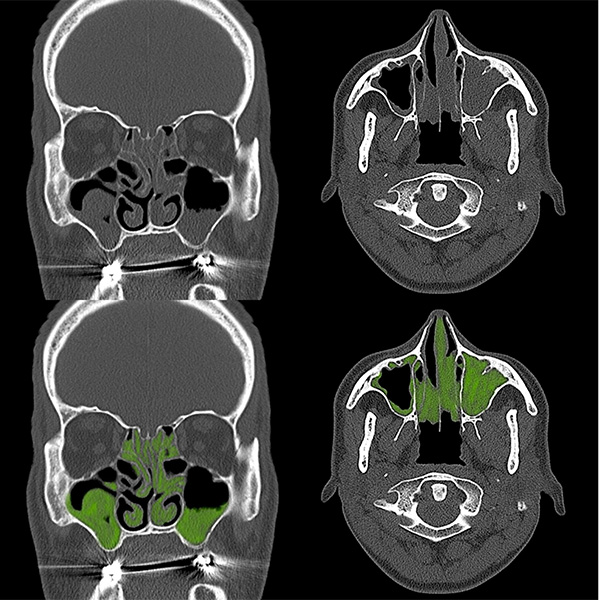

アレルギー性鼻炎・副鼻腔炎

Nasal examination

CT検査